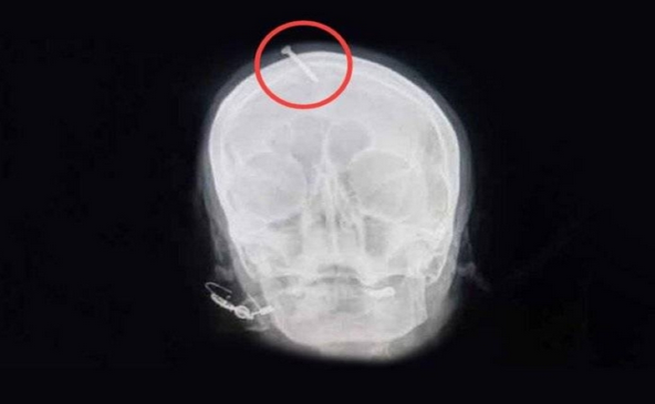

وأشار إلى أنها “كانت في كامل وعيها، لكنها كانت تعاني كثيراً”. وأظهرت صورة بالأشعة السينية أن المسمار اخترق الجمجمة خمسة سنتيمترات لكنه لم يصل إلى الدماغ.